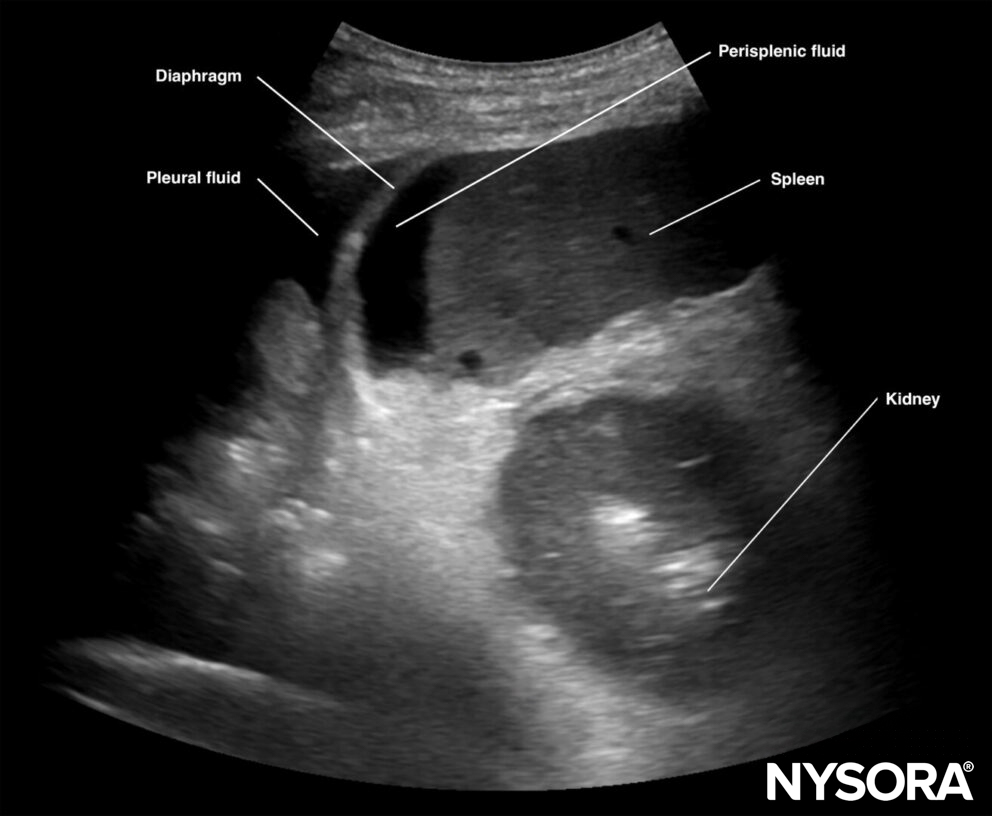

Free intraperitoneal fluid:

Intraperitoneal fluid often collects between the spleen and the diaphragm (perisplenic space). Fluid may also accumulate in other locations, such as the splenorenal recess. If intrathoracic free fluid is present, it can be identified above the diaphragm.

Free intraperitoneal fluid can be located in the perisplenic space.